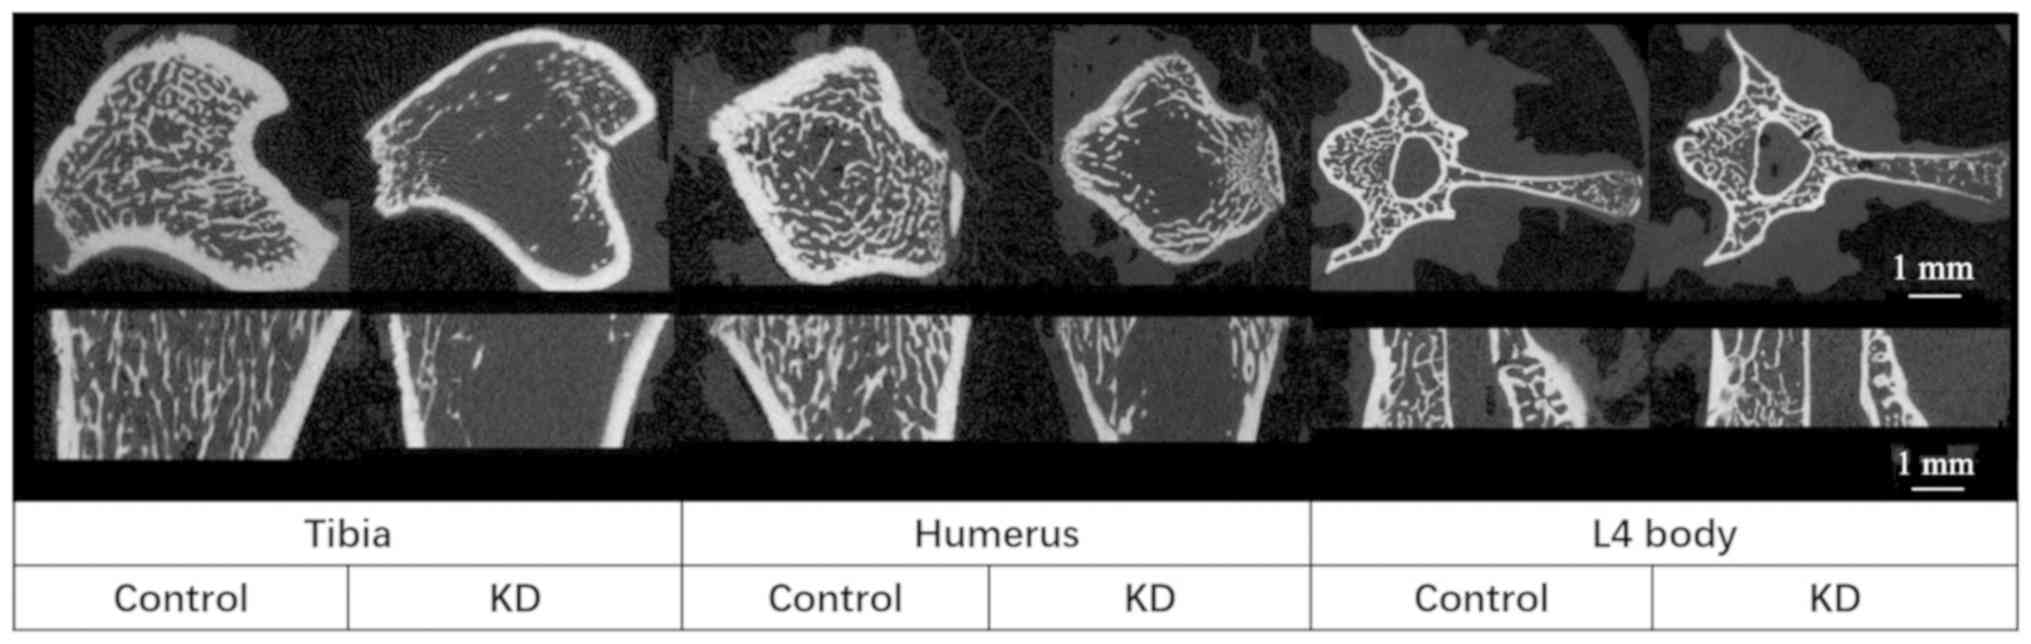

The KD group exhibited a decreased TBMD, BV/TV and Tb.N, and an increased Tb.Sp compared with that in the control group. In addition, trabecular thickness in the cancellous bone did not change between the groups, indicating that the trabecular structure became sparse following KD intervention (Table II; Figs. 2 and 3). These microstructural parameters were significantly changed in the tibiae and humeri of rats receiving the KD, whereas there were no significant differences in the L4 vertebral body samples between the groups (Table II; Figs. 2 and 3).

The Tarea and Barea were significantly decreased in the KD group (~20 and ~25% in the tibia and humerus, respectively) compared with those in the control group, whereas only a 10% decrease was obtained in the L4 vertebral body in the KD group, and there was no significant difference compared with the control group (Table II; Figs. 3 and 4). The only significant decrease in the Ct.Th was in the tibiae of rats from the KD group; while the largest decrease in Ct.Th was in the L4 vertebral body of KD group vs. control group rats (23%), this decrease was not significant (Table II; Figs. 2 and 3).

KD led to cancellous and cortical bone loss in the tibia and humerus, which was consistent with findings of tibia bone loss in a previous study by our group (14). A previous study by our group demonstrated that KD specifically caused cortical bone loss of tibiae in mice when compared with ovariectomized mice (14). The present study also investigated the bone loss in middle of L4 vertebra and the humerus, providing a comprehensive overview of the bone loss under KD. Furthermore, the present study revealed that the most severe trabecular bone loss and structural deterioration occurred in the metaphyseal area of the tibia, and was sensitive to the location selected. By contrast, similar cortical bone loss occurred in the tibia and humerus, while a lesser decrease was apparent in appendicular bones. In spite of greater microstructural changes in cancellous bone of L4 vertebral bodies in the KD group, the present study failed to detect significant changes, potentially due to the small sample size. However, the thickness of trabecular bone remained unchanged between the KD rats and the control group, which indicated a decrease in trabecular bone density associated with the bone loss.